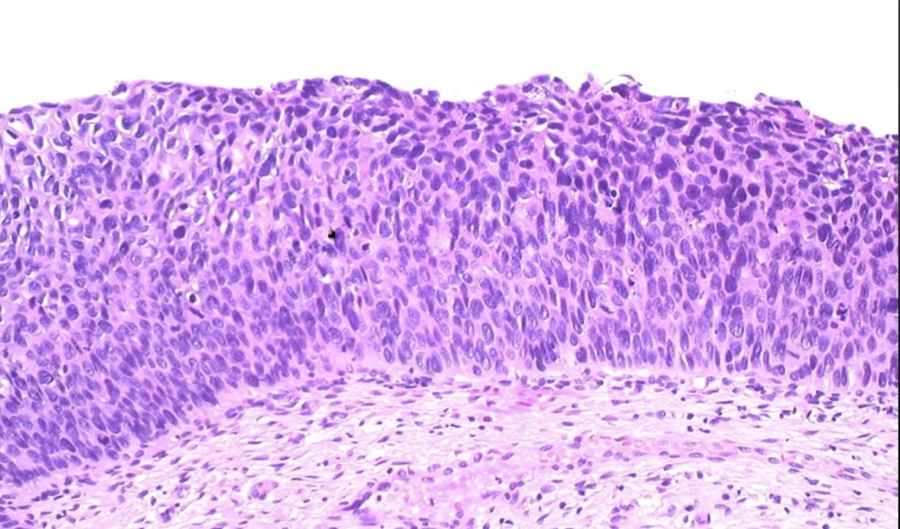

_Extramammary Paget Disease is characterized by malignant epithelial cells with pale cytoplasm and eccentric, hyperchromatic nuclei (Paget cells) in the epidermis of the vulva.

Extramammary disease, malignant paget cells infiltrating dermis. Epithelial near top. Looks like melanoma.

_The lesions of extramammary paget disease commonly present as erythematous, pruritic, ulcerated vulvar skin.

_Extramammary Paget disease represents carcinoma in situ (CIS), however, unlike paget disease of the nipple (breast involvement), there is usually no underlying carcinoma.

_It is very important to distinguish extramammary paget disease from melanoma, which is a lesion that rarely occurs on the vulva. The following histologic staining is used to make the differentiation:

Paget cells: PAS positive, keratin positive, S100 negative (Pas: mucous secretion from epithelial cells)

Melanoma: PAS negative, keratin negative, S100 positive